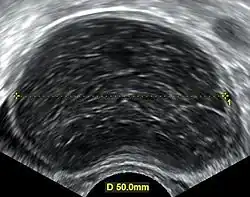

A 2 cm left ovarian cyst as seen on ultrasound

Ovarian cysts are usually diagnosed by pelvic ultrasound, CT scan, or MRI, and correlated with clinical presentation and endocrinologic tests as appropriate.[15] Ultrasound is the most important imaging modality, as abnormalities seen in a CT scan sometimes prove to be normal in ultrasound.[5][8] If a different modality is needed, then MRIs are more reliable than CT scans.[5]

Ultrasound

Usually, an experienced sonographer can readily identify benign ovarian cysts, often with a level of accuracy that rivals other approaches.[5]

Follow-up imaging in women of reproductive age for incidentally discovered simple cysts on ultrasound is not needed until 5 cm, as these are usually normal ovarian follicles. Simple cysts 5 to 7 cm in premenopausal females should be followed yearly. Simple cysts larger than 7 cm require further imaging with MRI or surgical assessment. Because they are large, they cannot be reliably assessed by ultrasound alone; it can be difficult to see posterior wall soft tissue nodularity or thickened septation due to limited ultrasound beam penetrance at this size and depth. For the corpus luteum, a dominant ovulating follicle that typically appears as a cyst with circumferentially thickened walls and crenulated inner margins, follow up is not needed if the cyst is less than 3 cm in diameter.[8] In postmenopausal women, any simple cyst greater than 1 cm but less than 7 cm needs yearly follow-up, while those greater than 7 cm need MRI or surgical evaluation, similar to reproductive age females.[16]